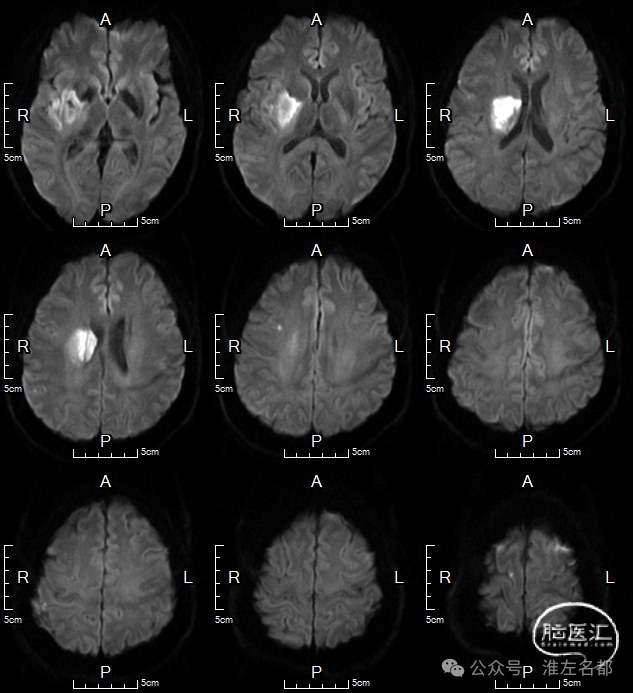

术后第3日MRI

DWI:右壳核、外囊和岛叶急性梗死。

颅脑MRA:未及明确异常。

术后症状快速改善,出院NIHSS:1